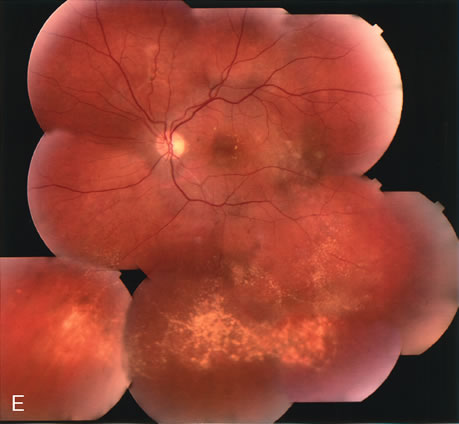

Clinically discernible peripheral dependent bullous neurosensory detachments have been described in patients with chronic CSC.85–92 Yannuzzi and co-workers first characterized the presence of RPE atrophic tracts extending inferiorly in the fundus periphery secondary to antecedent retinal detachment in patients with CSC.85 Presumably, there is a particularly severe and/or longstanding leakage of fluid from an RPE defect in the subretinal space at the posterior pole. The subretinal fluid gravitates inferiorly to form a dependent neurosensory detachment in a “flask,” “teardrop,” “dumbbell,” or “hourglass” pattern (Fig. 31). Sometimes the tract of subretinal fluid connecting the macular detachment with the bullous neurosensory detachment in the inferior hemisphere is so shallow that it is very difficult to appreciate. The RPE under the chronic retinal detachment experiences atrophic changes that appear as atrophic RPE tracts connecting the posterior pole with the dependent retinal detachment. The retina itself develops secondary manifestations including pigment migration, capillary dilatation (telangiectasia) proximally and capillary nonperfusion (ischemia) distally to the area of detached retina (see Fig. 31). The changes in the RPE consist of both RPE atrophy and pigment clumping in the form of perivascular deposits or bone spicules, a condition described by Gass as a “pseudoretinitis pigmentosa–like atypical CSC presentation.”87

Other complications noted in these patients are cystoid macular edema or, more frequently, cystoid retinal changes in the areas of chronic detachment, subretinal lipid deposition, choriocapillaris atrophy secondary to the RPE damage in the areas of RPE tracts, and CNV.89,90,204–206 This severe variant of CSC appears to be more frequent in patients of Latin or Asian ancestry, and it is usually associated with frequent recurrences, permanent central vision loss, and significant superior visual field loss. |